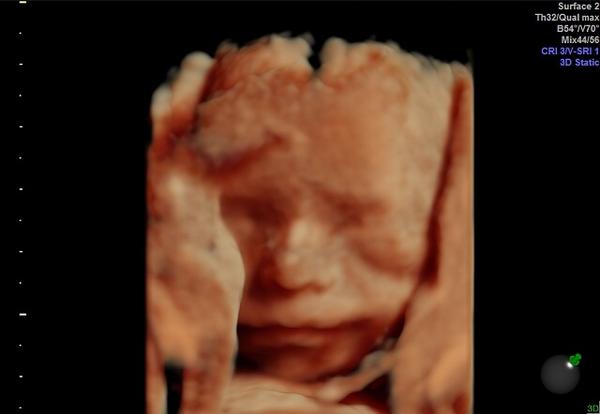

@simka2433 dopadli sme super, lekar povedal,ze je to dieta na jednotku, vsetko ako ma byt... a cakame na 100% dievcatko - Sofinku ☺️ pytala som sa, ci to uz urcite nebude chlapcek,tak povedal, ze v druhom kole, ze teraz urcite nie 😁 tak dufam, ze sa to nezmeni lebo bude spinkat v ruzovom😂😂